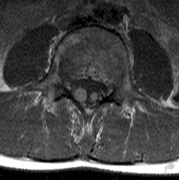

Intracranial leptomeningeal capillary vascular malformation (Figs. 21 and 22) is associated with seizures and contralateral neuromuscular weakness. Central nervous system involvement correlates highly with ipsilateral involvement of the V1 dermatome by a PWS.208,218

Fig. 22. Axial T2-weighted (a) and coronal T1-weighted (b) images of a 16-year-old boy with a port-wine lesion over the right side of his face. The right hemisphere is markedly atrophic and abnormal draining veins are seen within the right lateral ventricle (arrowheads). (c, d) The entire right hemisphere is covered by an enhancing pial angioma and the choroid plexi are enlarged. Enhancing retinal angiomas (arrows), typical of Sturge-Weber syndrome, are seen in (d).